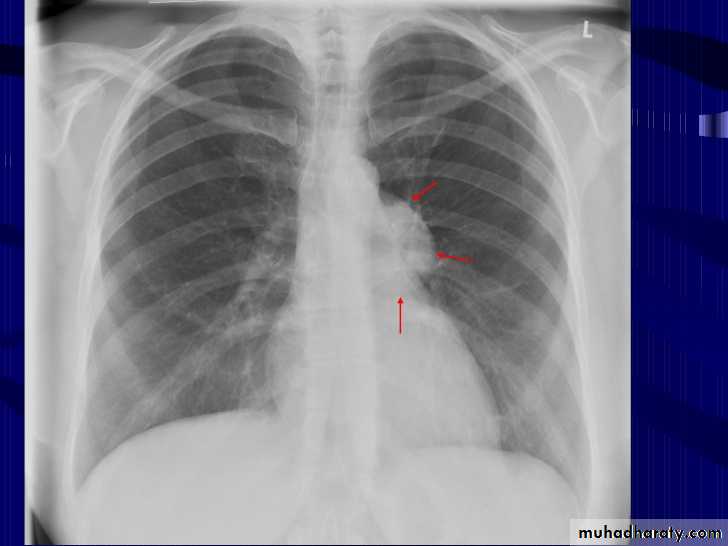

Mitral valve disease

Radiographic featuresPlain film

Typical radiographic features of mitral regurgitation include :

frontal projection

1.left atrial enlargement

convexity or straightening of the left atrial appendage just below the main pulmonary artery (along left heart border)

2.double density sign: the right side of the enlarged left atrium pushes into the adjacent lung and creates an addition contour superimposed over the right heart

3.elevation of the left main bronchus and splaying of the carina

4.upper zone venous enlargement due to pulmonary venous hypertension

5.left ventricular enlargement is also eventually present due to volume overload

6.Features of pulmonary oedema may also be present.